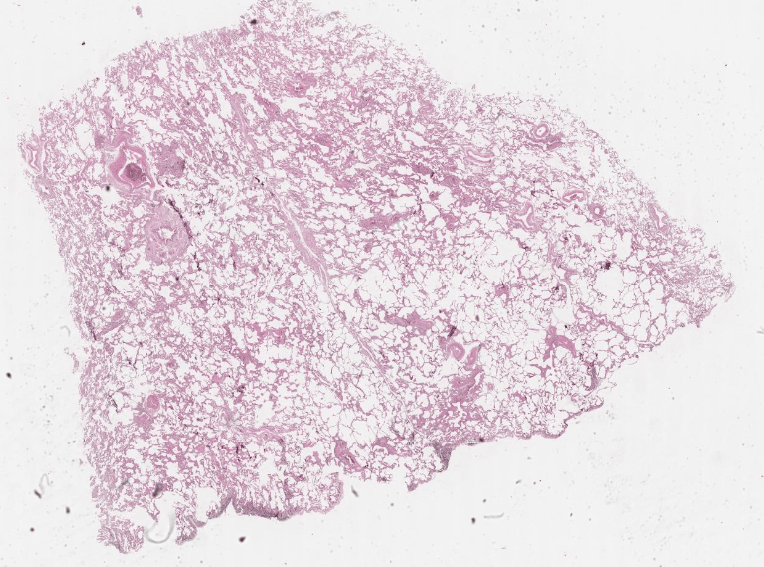

Видове емфизем?

Остър, хроничен, първичен, вторичен от учебника.

Старчески емфизем.

Липса на еластични влакна в белите дробове. Това е пример за атрофия на бял дроб, при който органа увеличава размерите си.